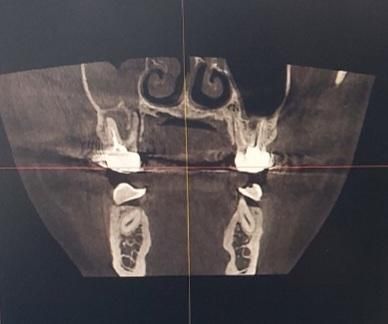

Ct촬영 영상입니다. 첫번째 사진의 경우, 윗니중에 오른쪽에서 3번째 치아가 문제가 되는 금니입니다. 해당 금니의 주변잇몸이 거의 녹아서 상악동과 염증이 연결된 형태라고 합니다. 또한 해당 치아의 뿌리는 총 3개인데 이 중 2개의 뿌리주변에 있는 잇몸은 거의다 녹았고, 나머지 1개의 뿌리 주변의 잇몸도 많이 녹았다고합니다. 이정도면은 재신경치료로 최대한 자연치아를 살리는 치료가 의미가 없으려나요..ct사진으로 정확히 판독해주시면 감사하겟습니다!

• 2번 째 사진

CT 영상은 여러각도와 분할로 봐야하기에 상기 이미지로는 한계가 있으나 이미 동요도가 어느정도 있는 상태라면 재신경치료로도 살리기 힘든 치아로 보임니다. 통증을 통반한 상태이면 활성화 상태이므로 발치가 적응증일거로 생각됩니다. 골소실이 더 진행되면 발치후 치유도 오래걸리는걸 감안하면 추후 임플란트를 고려중이시라면 빠른 결정이 나을것으로 생각됩니다.

현재 상태에서는 재신경치료를 하더라도 살릴 가능성은 매우 적습니다. 이미 상당 부분의 치조골이 소실되어 있는 상태입니다. 시간을 더 지체하게 될 경우에는 상악동까지 염증이 파급되거나 치조골이 더 많이 소실될 수 있으므로 늦지 않게 발치하는 것이 필요해보입니다.

만성 염증으로 인해 치아 뿌리 주변 잇몸뼈가 녹아있는 상태가 맞습니다. 이미 신경치료를 한번 한 상태인데 호전되지 않는 경우, 더 악화되는 경우 재신경치료의 성공률은 낮습니다.